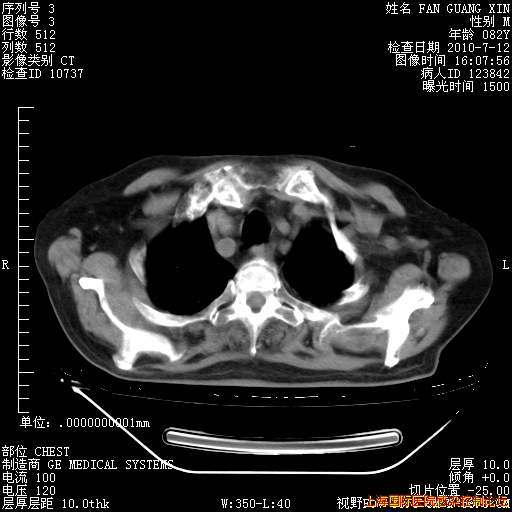

6月12日肺窗

6月12日纵膈窗